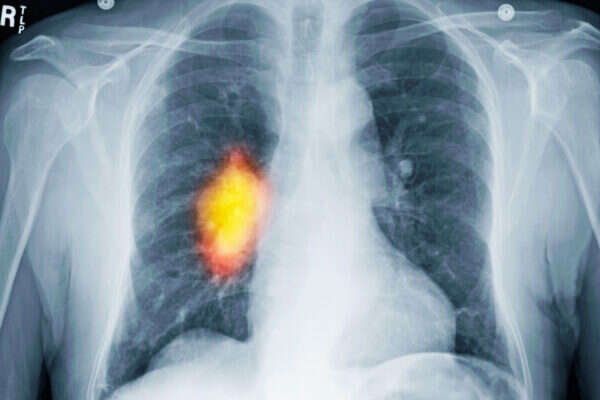

הפטנט של צוות החוקרים בראשות פרופ' אריה ציגלר עשוי להחליף את הקרנות הרנטגן הנפוצות כיום לטיפול בחולי סרטן. קרני רנטגן שחודרות לגוף האדם יוצרות נזק היקפי שהופך בעייתי במיוחד כאשר מדובר בטיפולים לילדים או לחולי סרטן במוח. טיפול בפרוטונים המואצים למהירויות גבוהות נחשב יעיל ובטוח יותר, מכיוון שהם נעצרים מייד עם הפגיעה בתאי הסרטן ואינם חודרים את הגוף כולו.